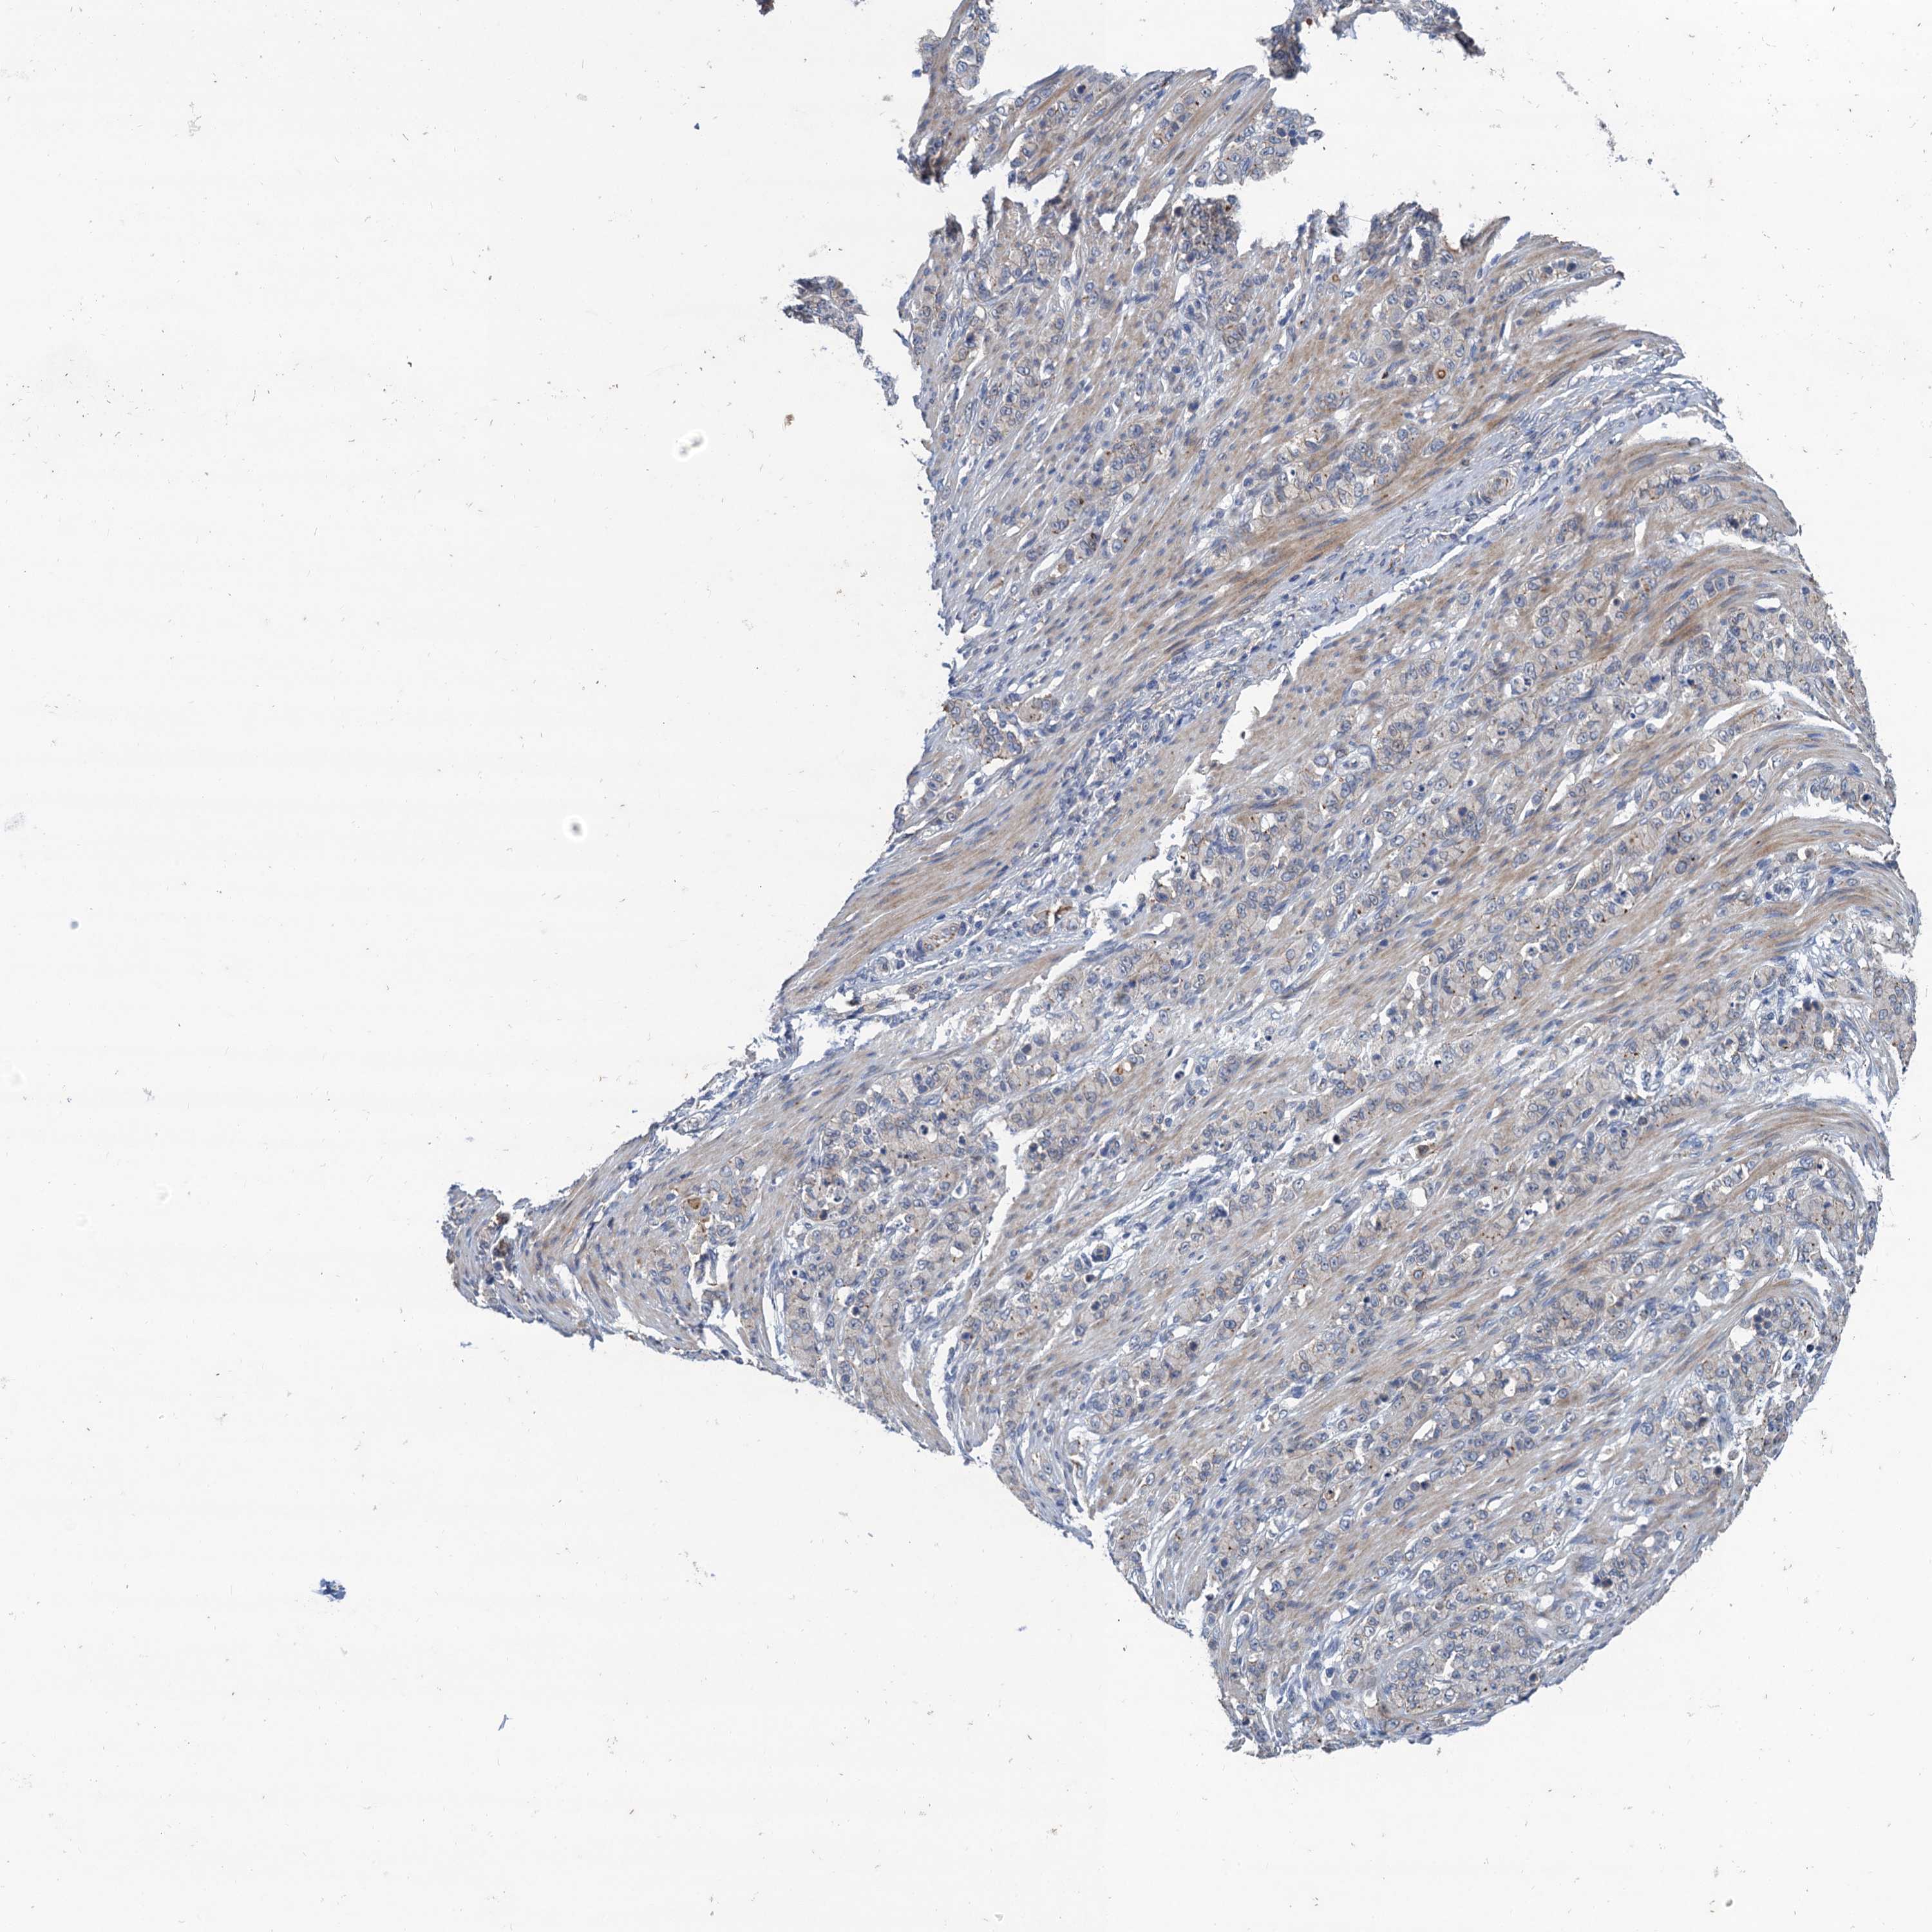

STOMACH CANCER - Protein expressioni

A mouse-over function shows sample information and annotation data. Click on an image to view it in a full screen mode. Samples can be filtered based on level of antibody staining by selecting one or several of the following categories: high, medium, low and not detected. The assay and annotation is described here.

Note that samples used for immunohistochemistry by the Human Protein Atlas do not correspond to samples in the TCGA dataset.

Antibody stainingi

Antibody staining in the annotated cell types in the current human tissue is reported as not detected, low, medium, or high, based on conventional immunohistochemistry profiling in selected tissues. This score is based on the combination of the staining intensity and fraction of stained cells.

Each image is clickable and will lead to virtual microscopy that enables deeper exploration of all samples and also displays staining intensity scores, fraction scores and subcellular localization as well as patient and tissue information for each sample.

Antibody HPA041229

Staining

High

Medium

Low

Not detected

Intensity

Strong

Moderate

Weak

Negative

Quantity

>75%

75%-25%

<25%

None

Location

Nuclear

Cytoplasmic/membranous

Cytoplasmic/membranous,nuclear

Adenocarcinoma, NOS

Adenocarcinoma, High grade